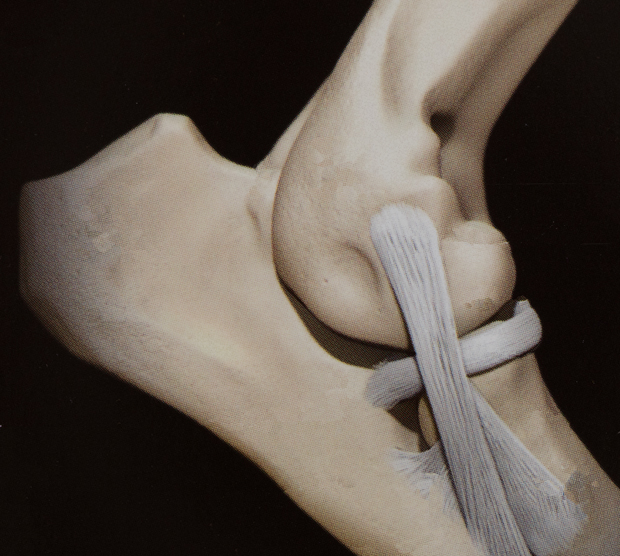

The elbow is known as the cubital joint and is created by the humerus, radius and ulna coming together in one joint. These three bones make the elbow somewhat different from the shoulder, hip and knee joints, in which only two bones are coming together to form a joint.

Normal elbow. Images courtesy of Long Beach Animal Hospital (LBAH).